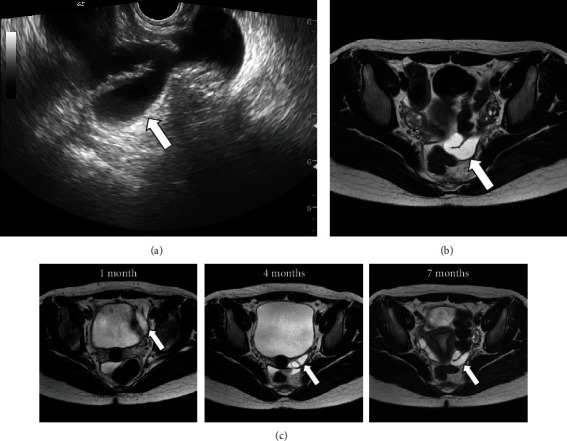

Case: A 15-year-old female patient with no history of abdominal surgery or sexual intercourse presented with acute left lower abdominal pain and purpura. MRI revealed hydrosalpinx in the left adnexal region. Her abdominal pain had completely resolved at our examination; she was followed up as an outpatient. One month after the initial presentation, she experienced a large volume of watery discharge. Magnetic resonance imaging, which was performed every three months, showed a gradual decrease in the size of the hydrosalpinx; however, it persisted in the left adnexal region. She was counseled to receive laparoscopy to treat the hydrosalpinx, which was the most likely cause of the watery discharge. IFTT was detected during the laparoscopy, and left salpingectomy was performed for pathological evaluation of the persistent hydrosalpinx. Following laparoscopy, the patient's watery discharge was resolved. Pathological findings confirmed no signs of malignancy.

Conclusion: Our current report highlighted watery discharge as an indicative symptom of IFTT. It is unclear whether IFTT induced the hydrosalpinx or vice versa. We presumed that the patient's hydrosalpinx occurred due to IFTT, because the patient complained watery discharge one month after the initial appearance, and noncongenital hydrosalpinx in adolescents, especially without a history of sexual intercourse, is a rare event. Clinicians should consider IFTT in patients presenting with unremitting watery discharge and hydrosalpinx, because IFTT may persist even after the pain disappears.